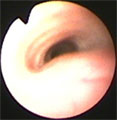

初診時胸部X線所見。胸部気管前部の扁平化およびLB1に結節影あり。 初診時気管支鏡所見。胸部気管前部に気管虚脱(GradeIII)あり。 第21病日。ステント設置後のX線所見。気管は拡張した。食道チューブあり。 第116病日の気管支鏡所見。肉芽形成・菌コロニーなし。固定糸がみえる。

経過:初診時、身体検査にて発熱なく、元気なく、飲水時誤燕あり。CBCおよび生化学で白血球数24000/μl、BUN 80.0 mg/dlと上昇、胸部X線所見で胸部気管前部が扁平化およびLB1に結節影あり、血液ガス分析ではpHa 7.415, Paco2 34.1 mm Hg, Pao2 91.5 mm Hgで正常。第6病日の気管支鏡検査にて頚部気管後部から胸部気管前部にかけ気管虚脱みられ、GradeIIIと診断した。LB1のブラシ生検では有意な細菌は検出されず、細胞診でも炎症・腫瘍なかった。飲水困難を伴った胸部気管虚脱GradeIIIと臨床診断した。内科治療を始めたがやはり飲水ごとに強くむせる症状あり脱水症状が生じた。第21病日、シリコン製の気道ステントを作成し設置した。同時に食道造瘻チューブを設置した。その後、内科療法(抗生剤、去痰剤、気管支拡張剤、ステロイド間欠投与)、ネブライゼーション、径チューブ輸液を行い、口からの飲水を制限した。術後、軽い乾咳が残るも苦しそうな状況は全くなくなり全身状態は改善した。1ヶ月後、自宅でネブライザーと径チューブ輸液を中心とした治療を行い咳症状はさら軽快した。第90病日、第116病日に気管支鏡検査にて経過観察を行ったが、ステント内に肉芽形成・菌コロニーの形成なかった。現在、約1年が経過しているが間欠的に自宅療法を行うだけでほぼ支障なく通常の生活をしている。